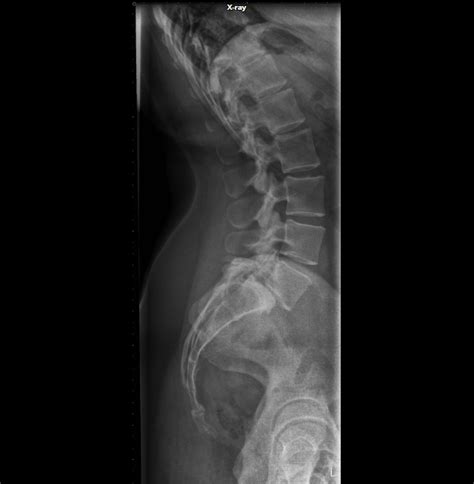

Proyección Lateral de Columna Lumbar

La proyección lateral es fundamental para evaluar la lordosis lumbar, la alineación de los cuerpos vertebrales y la integridad de los pedículos.

- RC: Perpendicular, dirigido a la tercera vértebra lumbar (aproximadamente 2.5 cm por encima de la cresta ilíaca).

- Casete: 14x17 pulgadas.

- Orientación: Longitudinal.

- Posición: Paciente en decúbito lateral, con el lado derecho o izquierdo en contacto con el chasis. El plano sagital del raquis debe ser paralelo al plano de la mesa. Las extremidades inferiores se flexionan para mayor comodidad y estabilidad.

- DFI: 40 pulgadas.

Estructuras Anatómicas Visualizadas: Cuerpos vertebrales lumbares en perfil, pedículos, apófisis espinosas y agujeros intervertebrales.

Criterios de Evaluación: Los cuerpos vertebrales deben observarse sin rotación. La lordosis lumbar debe ser visible. Los pedículos deben observarse como estructuras bien definidas y simétricas en cada vértebra. Los agujeros intervertebrales deben estar despejados.